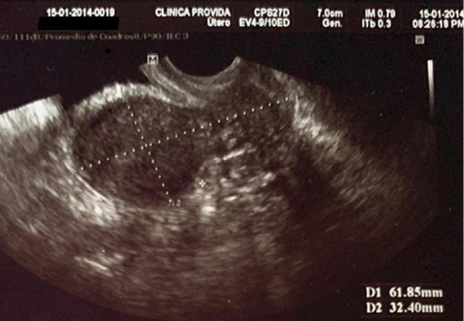

Antecedentes patológicos personales: incompetencia cervical, más aborto recurrente. Se observa la longitud cervical y longitud de útero previo al primer cerclaje en la Figura 1 y 2. Antecedentes quirúrgicos: cerclaje cervical por vía vaginal en la tercera gesta. Antecedentes gineco-obstétricos: menarquia 12 años, ciclos menstruales regulares, duración de 6 días, sangrado moderado. Gestas 4, partos 0, abortos 3, cesáreas 0, hijos vivos 0.

Figura 2. Longitud de útero por ecografía transvaginal

Fuente: Servicio de Ginecología-Obstetricia, Hospital PROVIDA